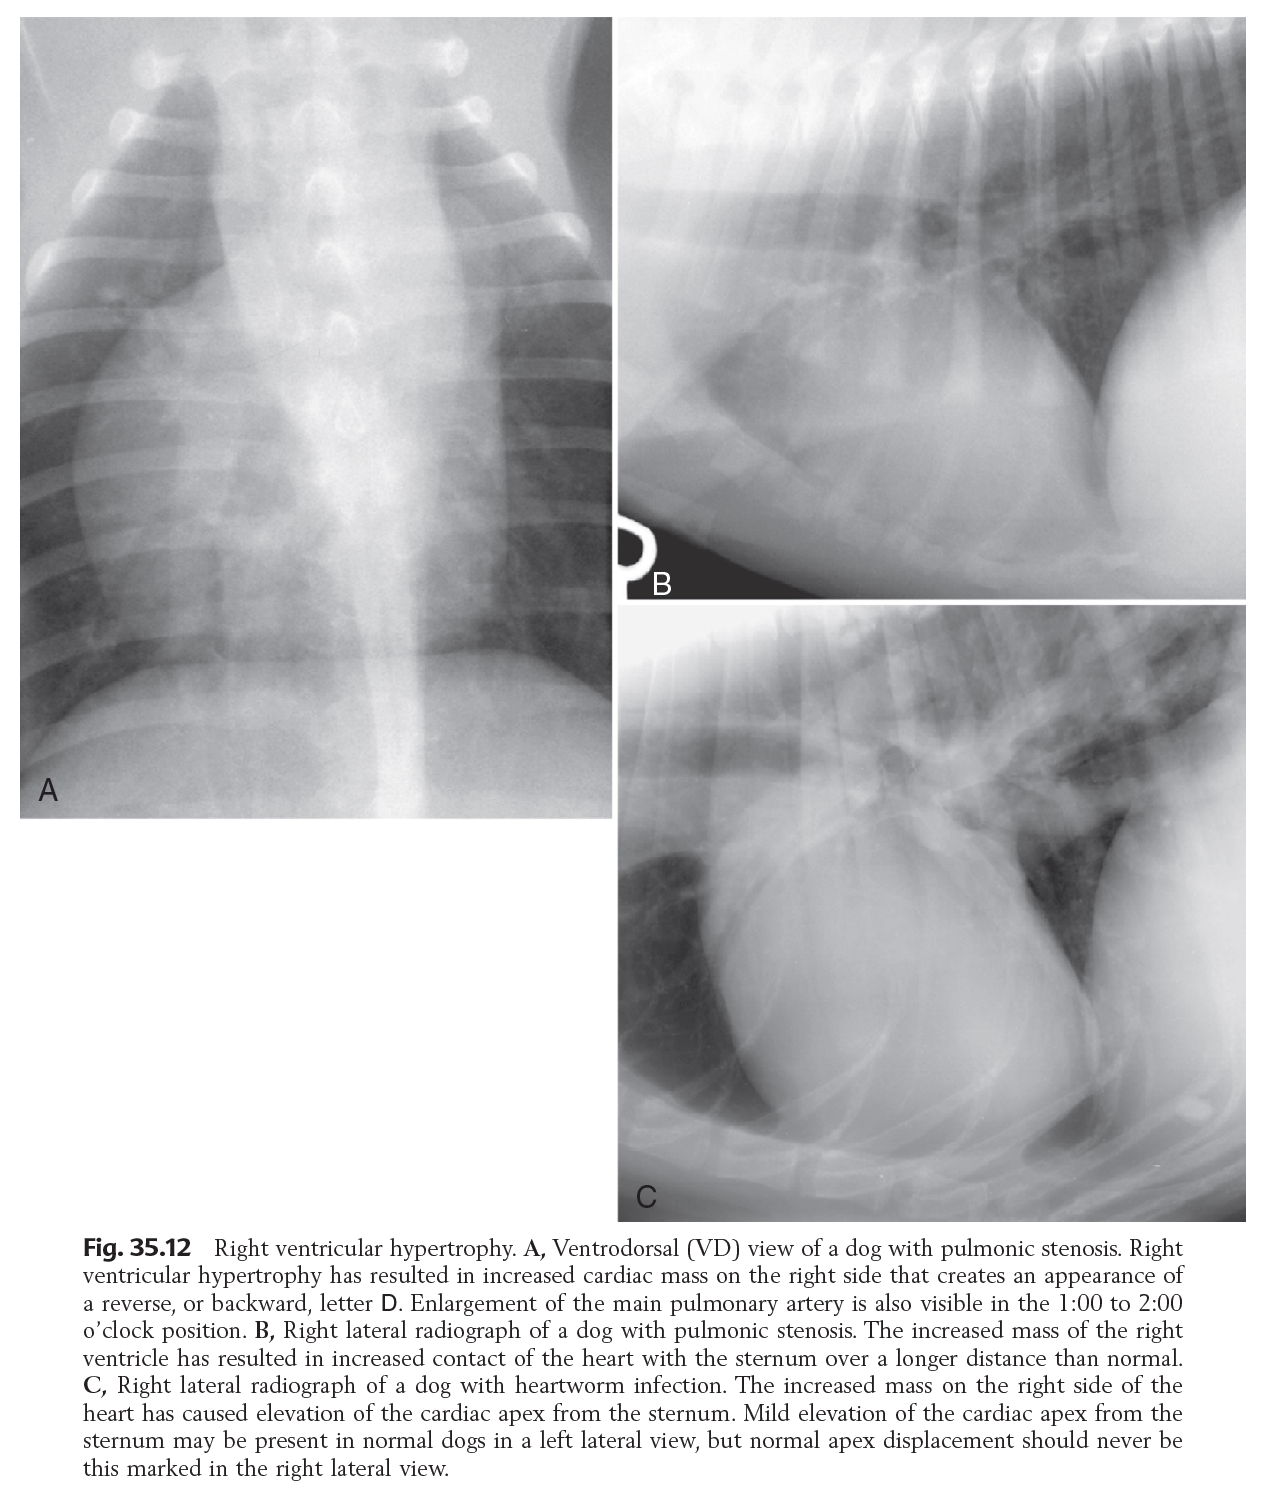

Hypertrophy of which chamber may be identifiable radiographically?

RV -> More so than LV

Possibly due to thinner wall -> more obvious changes

Rx features of RV Enlargement

Lat:

DV/VD

Causes of RV hypertrophy

INC AFTERLOAD: